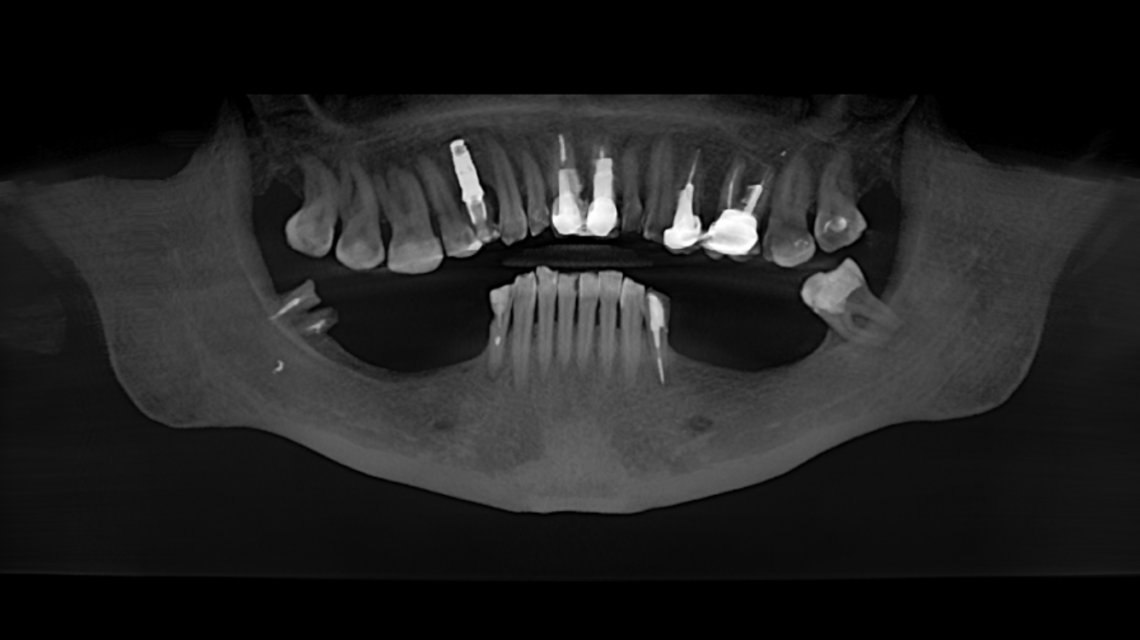

Планирование имплантации

рентгенографическое обследование (прицельная, панорамная рентгенография, компьютерная томография).